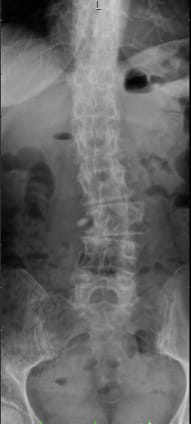

Compared to other implants, the viscoelastic disc prosthesis has the advantage that its design perfectly mimics the function of the natural disc. Furthermore, extensive laboratory testing has proven that it has a durability of at least 50 years. Whether and how surgical treatment of the affected vertebral segments should be carried out is planned individually by the specialist after thorough diagnosis (MRI, CT, X-ray, physical and neurological examination). If, for certain reasons, partial fusion of a section of the spine is unavoidable, this should be limited to one segment as far as possible, as shown in the following example. In this way, the greatest possible functionality of the spine can be maintained or restored.

Postoperative status: Complete axial correction of the lumbar spine with two disc prostheses and a PEEK cage. Normal lordosis of the lumbar spine also visible in the lateral view after the operation. (Spine Centre Rischke)

(2) Example of treatment with a viscoelastic disc prosthesis and dynamic fixator in the presence of spondylolisthesis